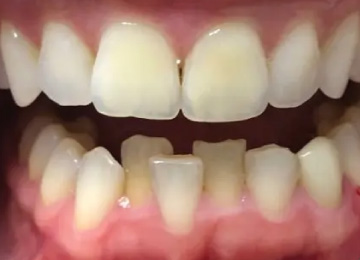

Капа для зубов: фото До и После

Фото ДО

Фото ПОСЛЕ

Наведите для просмотра

Капа для выравнивая зубов